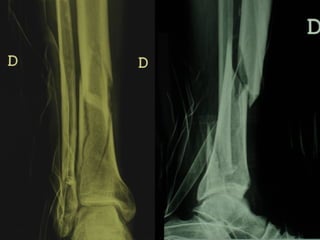

Dal Gennaio 2000 al Febbraio 2006 abbiamo trattato 167 fratture chiuse  con placca percutanea  in 164 pazienti :  27 lesioni diafisarie di gamba, 12 piloni tibiali ,  11 fratture prossimali di tibia, 36 fratture sovracondiloidee di femore, 17 fratture diafisarie di femore, 43 fratture metaepifisarie prossimali di omero, 21 diafisarie d’omero.  156 guarigioni 8 fallimenti

Dal Giugno 2002 al Dicembre 2004 abbiamo trattato 5 fratture esposte: 3 di tibia e 2 di ulna 5 guarigioni

I buoni risultati ottenuti dipendono da 5 punti fondamentali:   una accurata riduzione percutanea della frattura  precise vie di accesso  l’utilizzo della placca che consenta il più lungo braccio di leva possibile il pretensionamento della placca  una sintesi con un ridotto numero di viti

Fratture  esposte